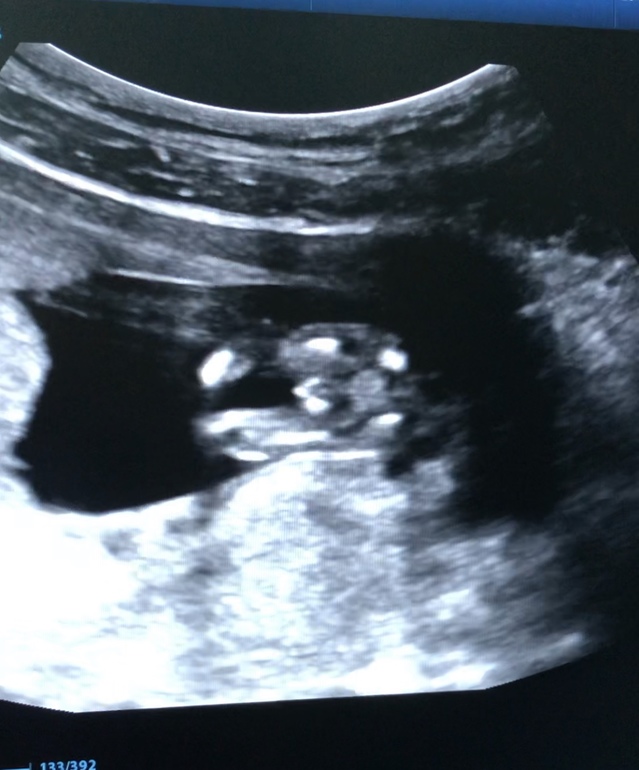

Вопросы про УЗИ, обследования и анализы: что, где, как, когда?Впервые пишу в это сообщество!) прошла несколько дней назад 1 скрининг на сроке 12.5 недель)) все по результатам хорошо, предположили пол -сказали похож на мальчика) хотела спросить, может кто разбирается либо опытные многодетные мамочки у которых есть тоже фото на таком сроке, как думаете на кого больше похож ? Я почему в мальчике не уверена

13 недель ровно. Врач сказала что девочка. Специально развернула этим местом и сфотала.

По-моему, мальчик. Весьма так явно орган торчит:)) Но у друзей «100% мальчик» после 20 недель неожиданно трансформировался в девочку. Так что все бывает.

Как то на мальчика больше похож,у девочек то тоже может торчать половой бугорок но мне кажется не настолько

У меня пять мальчиков. Ракурс шикарный. Обычно такое фото делают для тех, кто сомневается. Мальчик у Вас 120%